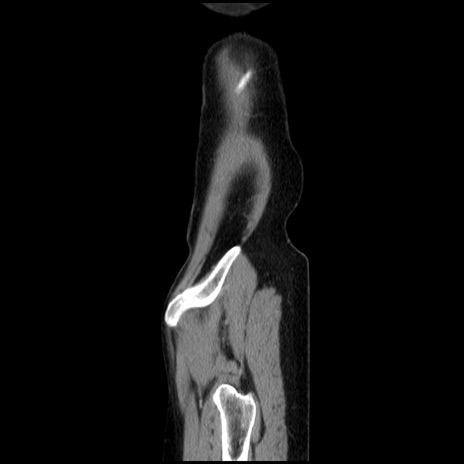

【症例】40歳代 女性

【主訴】上腹部痛、嘔気・嘔吐

【現病歴】約9時間前頃から急に上腹部痛、嘔気、嘔吐が出現。改善しないため救急要請。

【既往歴】子宮頚癌(広汎子宮全摘術、放射線療法)、腸閉塞

【身体所見】腹部:平坦、軟、腸雑音亢進、上腹部を中心に腹部全体に圧痛あり。

【データ】WBC 8400、CRP 0.03